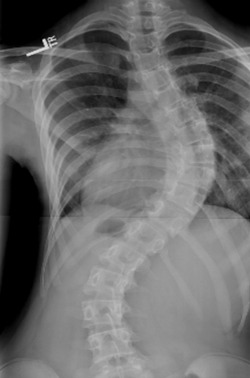

Scoliosis

If you are an adult living with scoliosis, you should definitely be under chiropractic care. Every place your spine “kinks” or curves is a place that is under more strain and pressure. Since gravity is a constant force and is always applying pressure to the spine, the more in alignment your spine is the better.

With these increased curves, your spine is under tremendous extra pressure. Think about trying to hammer in a bent nail. In this scenario, the spine is the nail and gravity is the hammer. There will also be constant pressure on the areas that are not lined up correctly and it is very important that you keep your spine moving and functioning at its best.

X-ray analysis will be important to see which areas can be adjusted. While you would not be in danger of the chiropractor breaking any of the surgical screws, there’s no reason to have attempts to adjust those areas if it is not necessary. We can and will also use some adjusting instruments or specialized tables to adjust your spine without any unnecessary twisting or awkward, uncomfortable positions.